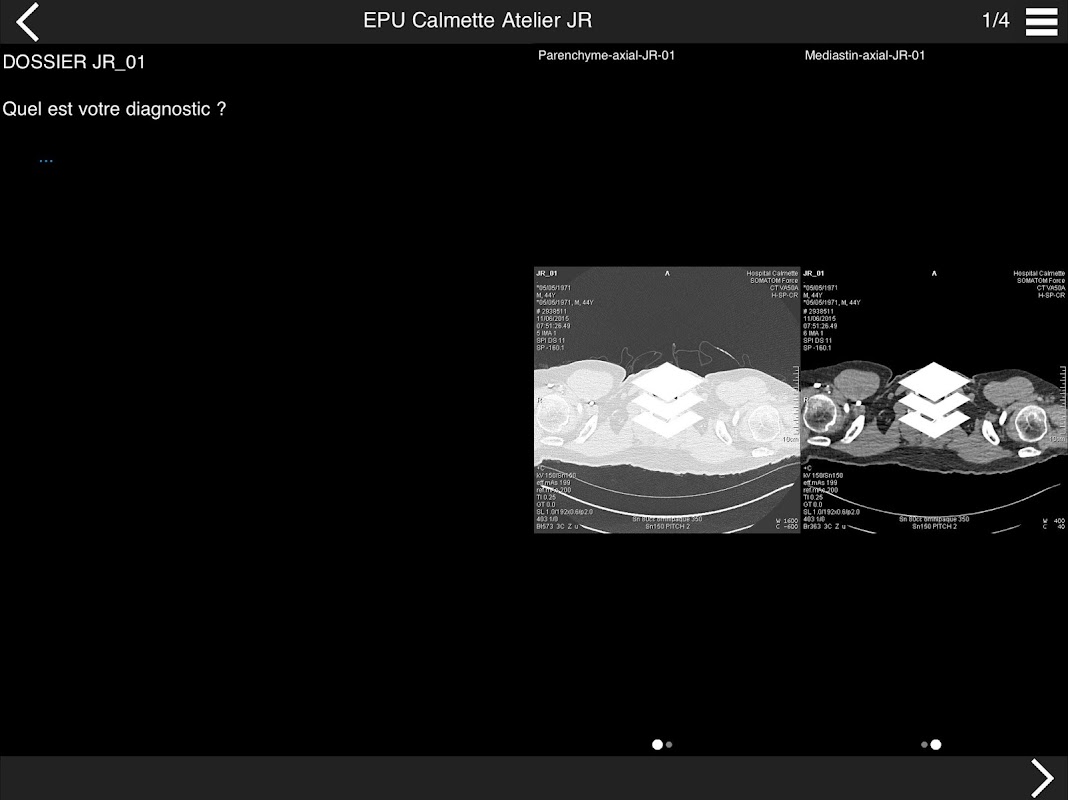

Retrouvez les cas cliniques du Cours intensif de TDM multicoupe du thorax dans cette application.

• DE LA SéMIOLOGIE AU COMPTE-RENDU

* BPCO et nodules pulmonaires : recommandations en 2017

* Pathologie interstitielle : lésions élémentaires et « patterns »

* Pathologie vasculaire et médiastinale

* Oncologie thoracique : bilan standard et introduction à l’étude de l’angiogénèse